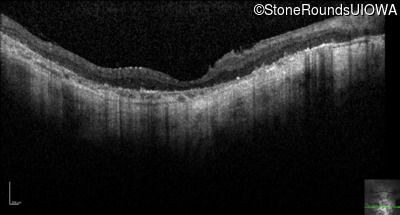

Optical Coherence Tomography - Right - Hand Motion @ face sc

Exemplar / OCT Stack